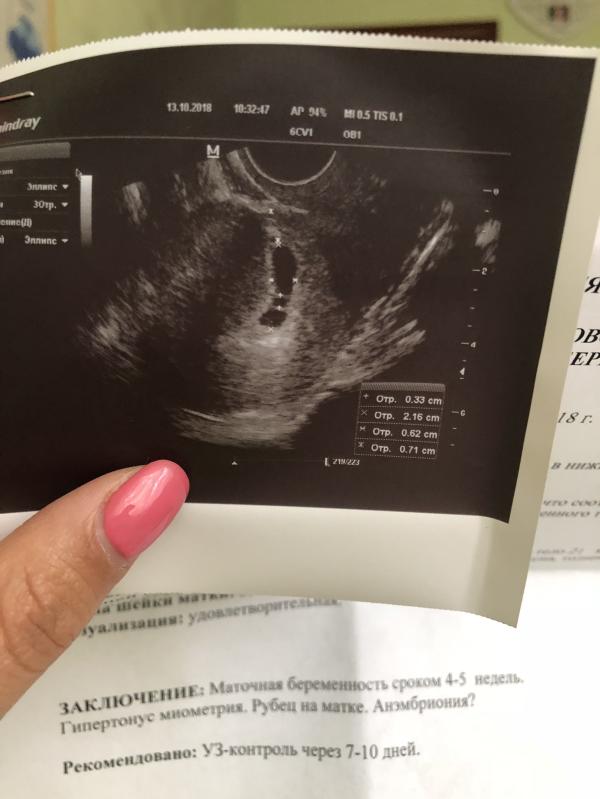

Как сделала узи утром и не понимаю что происходить 😩только читаю , внутри так грустно хочется плакать, не хочу чтобы в третий раз мне сказали что зб😟

@mammy_romeo, я переживаю потому что она сказала плодное яйцо деформировано 😟